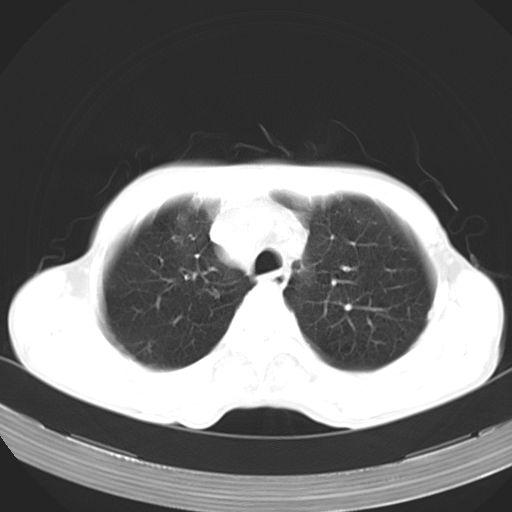

以下是引用苯小孩在2007-5-24 12:47:00的发言:[br]右侧肺门处不均匀密度软组织块影,远端肺组织见斑片模糊影,纵隔内淋巴结明显肿大,边界不清.<纵隔窗第12层面支气管内似见软组织结节>[br]考虑:1、右侧中央性肺癌并阻塞性肺炎并纵隔淋巴结转移可能性大.建议强化或纤支镜进一步检查.[br]2、隆突下淋巴结肿大/食道病变?请做鉴别检查.

以下是引用zhangzhongshou在2007-5-24 12:55:00的发言:[br]1、右肺中叶中心型肺癌并右肺门、隆突下、纵隔淋巴结转移。右肺中叶阻塞性肺炎。

以下是引用jw-830在2007-5-24 15:24:00的发言:[br][br] [br] 考虑右肺中央型肺癌并阻塞性炎症,右肺门及纵隔淋巴结转移。 [br] [br][br]